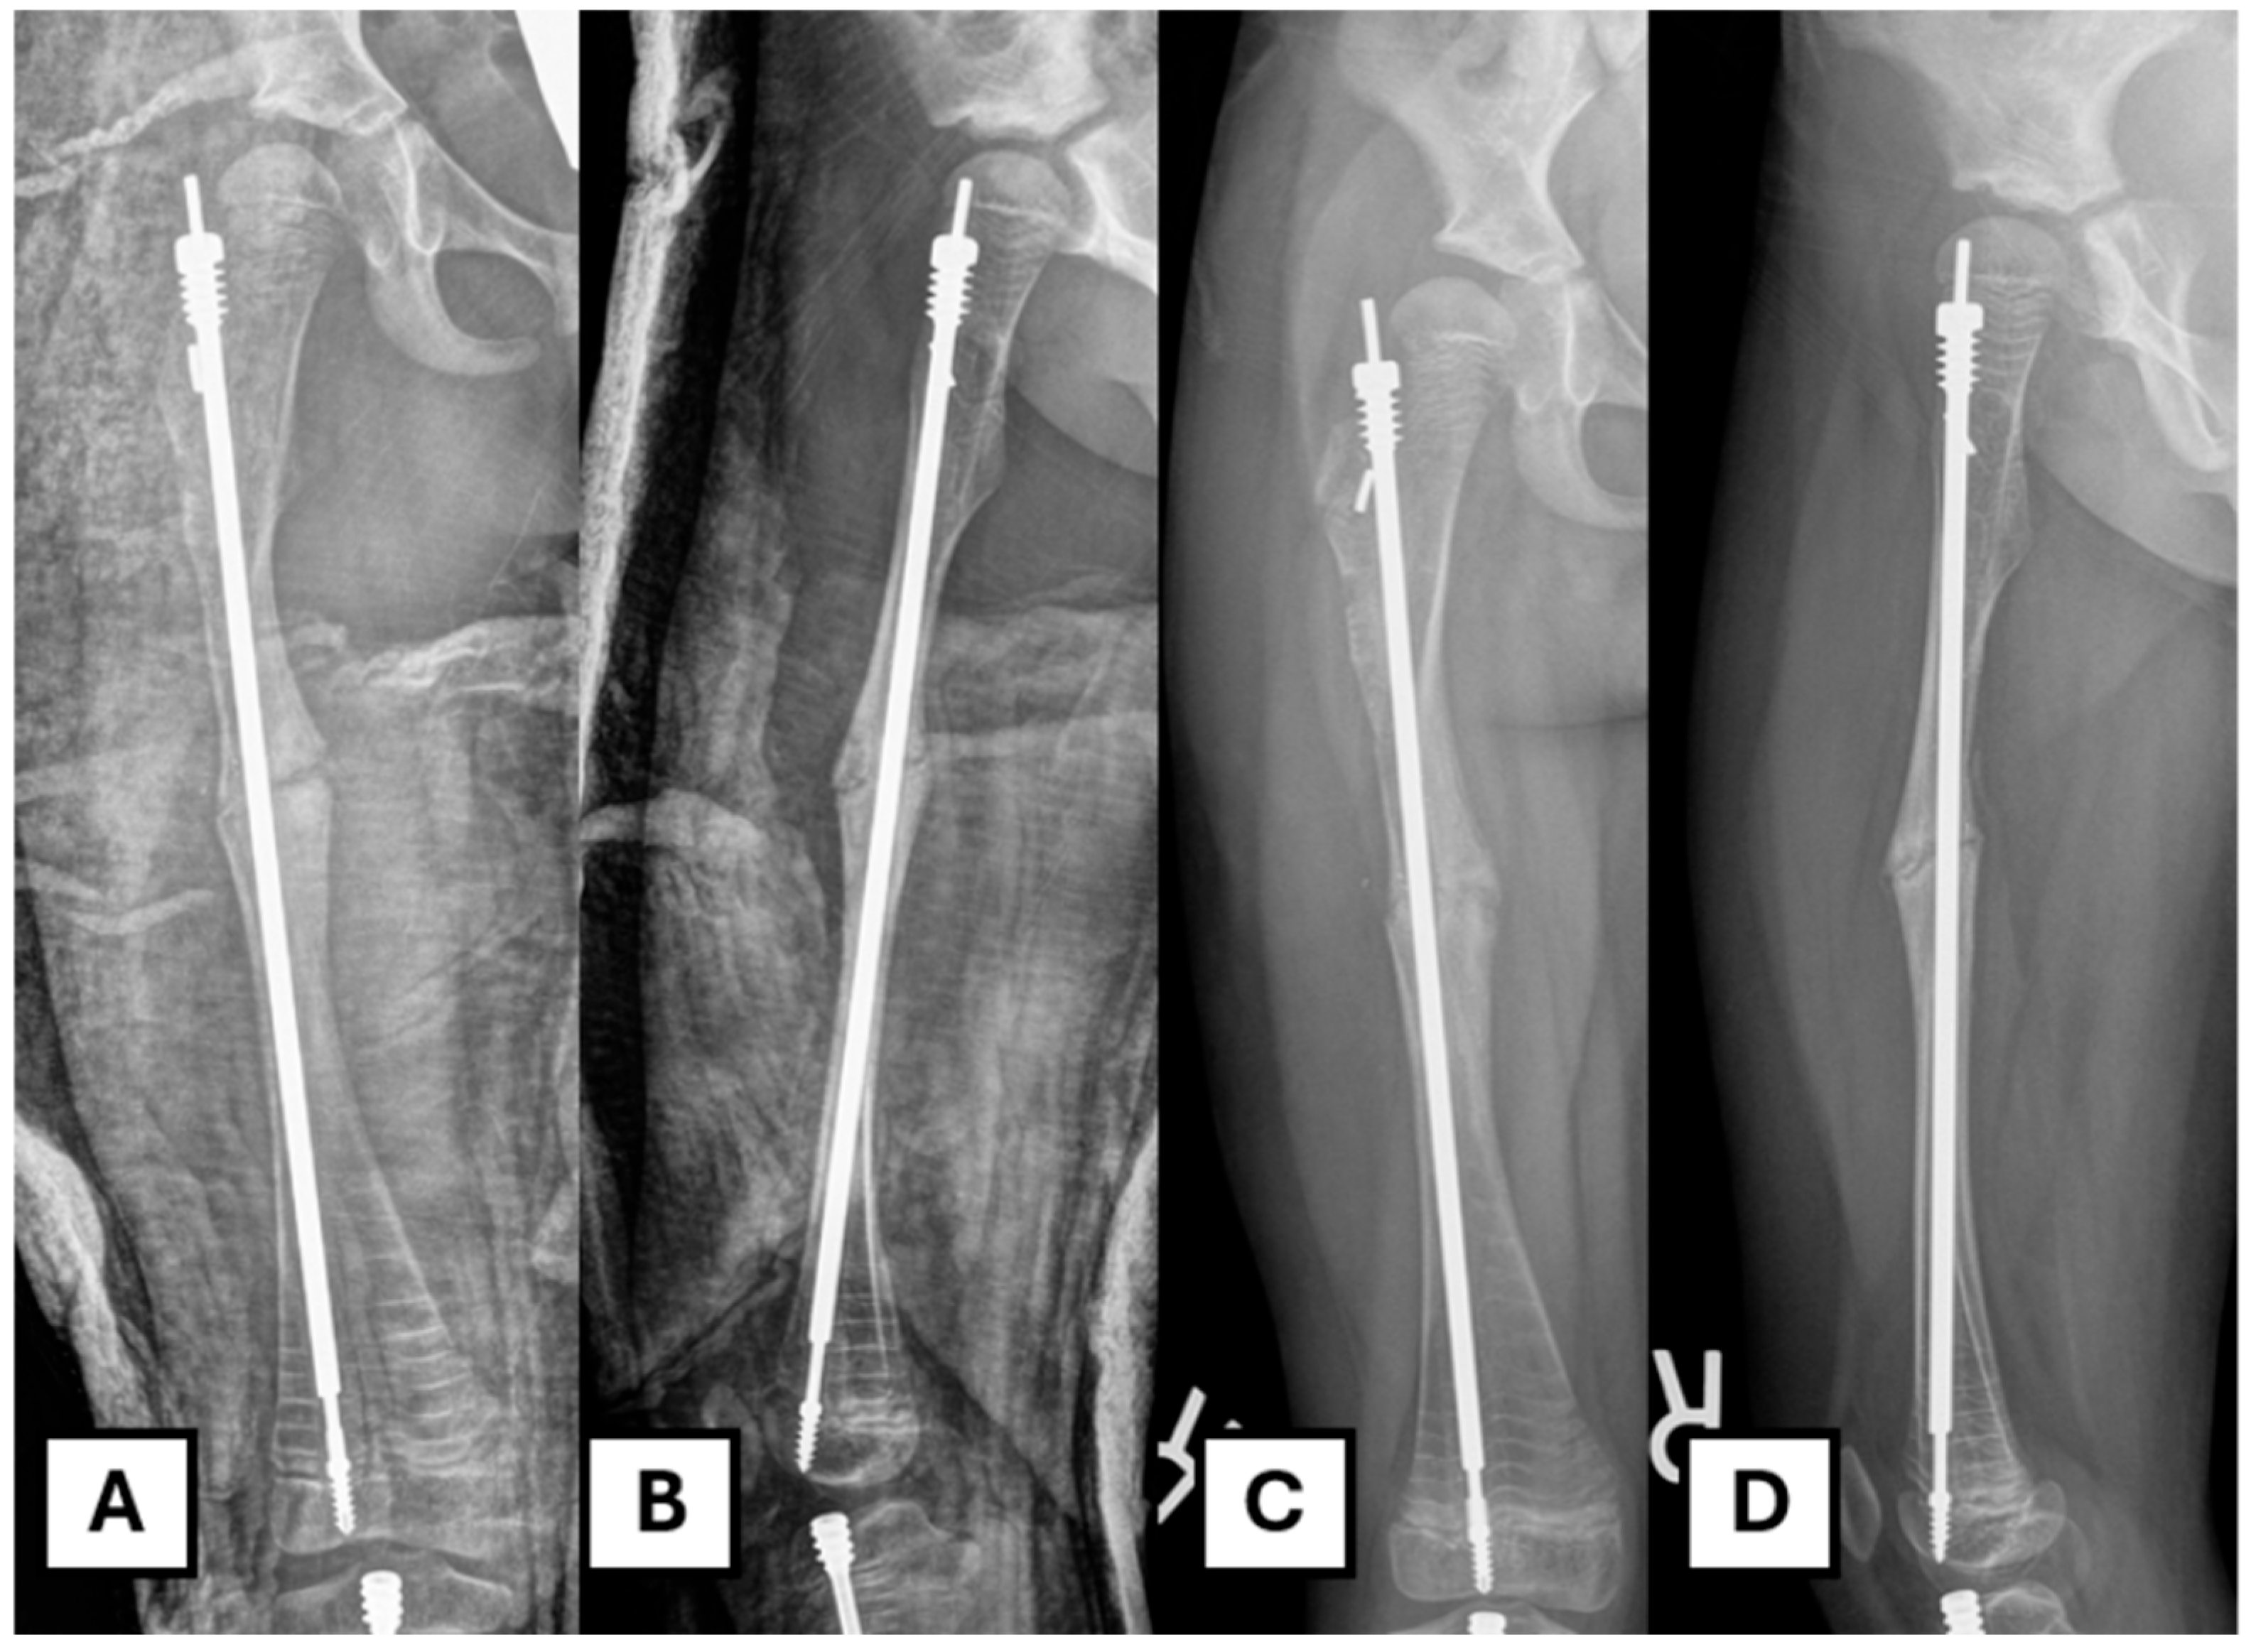

A standard subvastus posterolateral approach to the femur is utilized. The skin is incised with a size 15 blade. A self-retainer is used to expose the subcutaneous fat, which is divided using cautery down to the level of the fascia. A Cobb elevator is used to sweep fat from the line of incision in the fascia, and it is incised longitudinally to the extent of the skin incision both proximally and distally. The periosteum is split, and the Cobb elevator is used to perform a sub-periosteal dissection. Broad Hohmann retractors are placed to expose the fracture/osteotomy site (Figure 2A). A straight osteotome is employed to open the fracture site (Figure 2B). The callus that is formed around the fracture site was removed to expose the fracture end. The fracture site/osteotomy site is then distracted with a laminar spreader. It is critical to distract slowly and gently, as forceful distraction, especially in a poor-quality bone or a more severe OI type, might lead to iatrogenic fracture. The underlying rod is then revealed. (Figure 2C).

The patient is admitted overnight for pain control. Two doses of post-operative prophylactic antibiotics are administered. A standard AP and lateral X-ray of the operated femur is obtained on day one post-op. The patient remains non-weight-bearing on the operated leg for six weeks post-op. A follow-up in the clinic is performed two weeks after the initial visit, at which point the wound is reviewed. A decision is made regarding the progression of weight-bearing status when the X-ray shows adequate healing (Figure 6).

Figure 6. Post-operative image after revision. (A,B) Immediate post-operative radiograph. (C,D) Six weeks post-operative radiograph showing progression of osteotomy site healing.